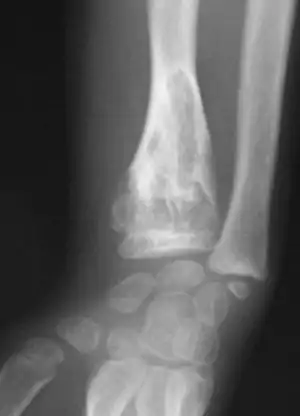

| X-ray image showing enchondromas localized in the lower part of the radius of a 7-year-old girl with Ollier disease. | |